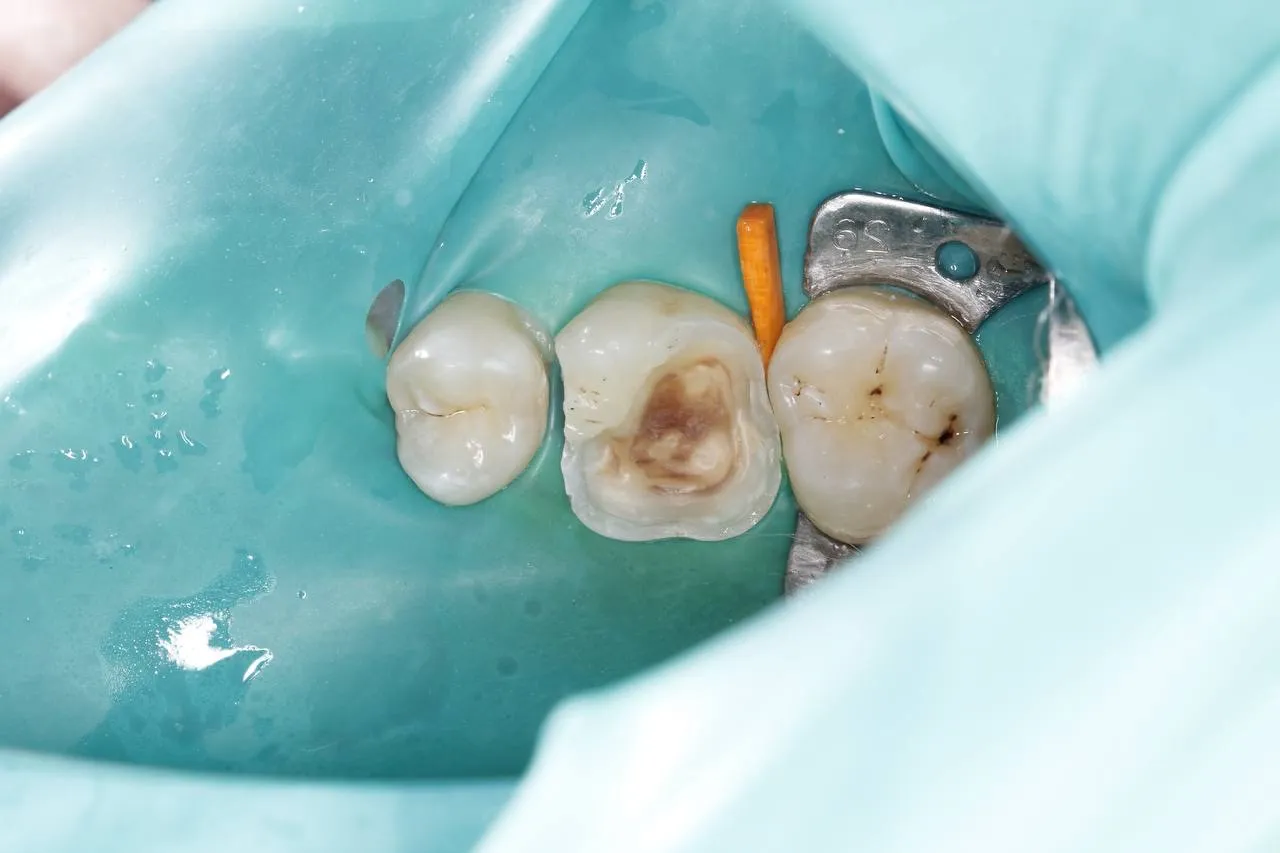

Лікування карієсу під мікроскопом зуба 16